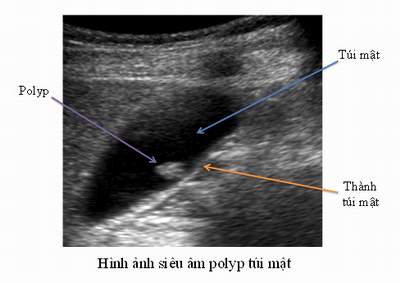

Trả lời: Rất thông cảm cho câu hỏi của anh và gia đình, thực chất ra cũng không có gì nghiêm trọng nếu nó là polyp túi mật lành tính. Theo các bác sĩ chuyên khoa gan mật cho biết polyp túi mật còn gọi là u nhú niêm mạc tuyến mật, là một dạng tổn thương dạng u hoặc giả u phát triển trên bề mặt niêm mạc túi mật. Đây là một bệnh khá phổ biến, chiếm tỷ lệ tương đối, có thể xuất hiện ở mọi lứa tuổi và không có sự khác biệt đáng kể về tỷ lệ mắc giữa nam và nữ, dân tộc. Đặc biệt các hình ảnh này nhìn thấy thường qua sàng lọc khám sức khỏe định kỳ hàng năm, có tầm soát siêu âm bụng tổng quát, phát hiện tình cờ.

Polyp túi mật là thuật ngữ chuyên môn y học để mô tả các hình thái tổ chức xuất phát từ thành túi mật phát triển lồi vào trong lòng túi mật. Các hình thái tổ chức có bản chất cấu trúc khác nhau, có thể là lành tính hoặc không lành tính (ung thư). Polyp túi mật lành tính chiếm khoảng 92% các trường hợp, gồm có hai loại: u tuyến như adenoma, leiomyome (u cơ), lipome (u mỡ)... u giả như cholesterol polyp (u cholesterol), andenomyomatosis (u cơ tuyến), viêm giả u... Polyp túi mật ác tính chiếm khoảng 8%, gồm có adenocarcinoma (ung thư tuyến), mealanoma (u sắc tố), di căn ung thư... Số lượng và kích thước của polyp túi mật cũng khá đa dạng, nhưng thường gặp nhất là có một polyp trong túi mật với kích thước nhỏ hơn 10 mm. Một số người (rất ít) có thể có nhiều polyp trong túi mật hoặc kích thước polyp lên đến 20-40 mm, hay vừa có polyp vừa có sỏi túi mật. Tuy vậy trên thực tế, polyp túi mật chủ yếu gặp ở người trưởng thành, rất hiếm gặp ở trẻ em. Tỷ lệ polyp túi mật trong cộng đồng dao động từ 0,03 - 9%. Nếu so với sỏi túi mật thì polyp túi mật ít gặp hơn sỏi túi mật, hay gặp ở phụ nữ độ tuổi từ 30-50.

Vì vậy chẩn đoán chủ yếu dựa vào các thăm dò cận lâm sàng. Hiện nay với sự phát triển của các phương tiện chẩn đoán hình ảnh: siêu âm, siêu âm nội soi, chụp cắt lớp vi tính (CT- scanner), chụp cộng hưởng từ hạt nhân (MRI) đã giúp ích rất nhiều cho chẩn đoán polyp túi mật, phân biệt với các hình ảnh khác trong cơ quan gan mật. Trong các thăm dò chẩn đoán phổ biến trên thế giới nêu ở trên thì siêu âm vẫn là phương pháp được lựa chọn chính. Trên siêu âm có thể phát hiện thấy hình ảnh tăng âm bám dính trên bề mặt túi mật, không có bóng cản và không thay đổi theo tư thế người bệnh, đây là dấu hiệu để phân biệt với sỏi túi mật. Mặc dù có độ nhạy và độ đặc hiệu khá cao, nhưng siêu âm không thể phân biệt được là polyp lành tính hay ác tính để có chỉ định điều trị phẫu thuật. Các phương pháp khác cũng được sử dụng như chụp cắt lớp vi tính, siêu âm nội soi nhưng độ đặc hiệu không cao nên còn đang được bàn cãi.